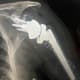

A postoperative radiograph shows a revision reverse total shoulder arthroplasty..